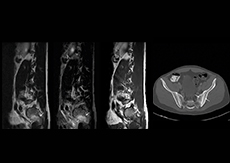

“In our lumbar spine MRI, the value of mDIXON TSE is so obvious. Normally we perform T1 and T2 scans in sagittal and transverse orientation.It used to take too much time to add a sagittal T2 with good fat suppression.But now, using mDIXON TSE, we get the sagittal T2 fat suppressed images ‘for free’, that is: without adding time.”

“Diagnostically that is a great benefit. I sometimes see abnormalities in the fat suppressed sagittal T2 that would be quite challenging to notice in the T2 without fat suppression. There have been several diagnoses that I could make easier because of our exam setup with mDIXON TSE, such as sacrum insufficiency fractures and sacroileitis; these were more challenging with our previous exam setup.”